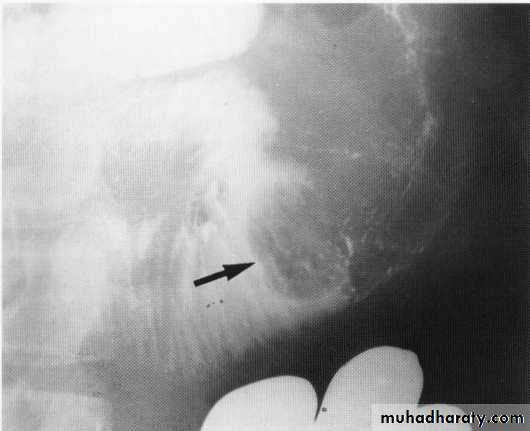

Leiomyoma Ba swallow